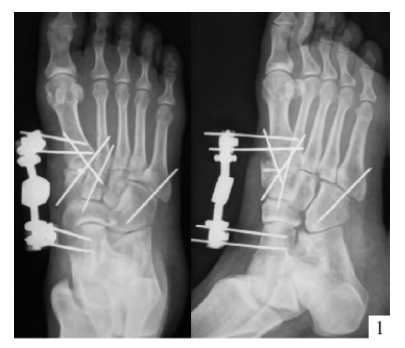

内固定选择1、克氏针:优点是手术简单、时间短、对周围组织损伤小,缺点是固定不坚强、复位丢失等情况时有发生。2、可吸收螺钉:优点是不需行二次手术取出内固定物,缺点是固定强度不及传统螺钉3、小螺钉系统:经典 --- 3.0mm、3.5mm、4.0mm4、空心螺钉:3.0mm、4.0mm、4.3mm 、4.5mm5、微型钢板:跨关节固定,对于严重的跖骨粉碎性骨折的患者,螺钉无法固定时,建议选择微型钢板桥接固定6、骑缝钉

手术切口选择单一切口、双切口

双切口能充分显露所有的跖跗关节;第一切口位于第一、二跖骨之间。该切口利用了两个间隙,一个拇长伸肌腱内侧,一个为拇短伸肌腱外侧。分别可显露第一跖骨、内侧楔骨和第二跖骨、中间楔骨。通过延长皮肤切口,可以直视第三跖骨和外侧楔骨。第二切口位于第四、五跖骨之间,可以显露其与骰骨之间的关节。

根据三柱理论1、首先复位内侧柱并临时固定 2、再复位固定中间柱3、如外侧柱移位可能需双切口

手术从第一跖骨和内侧楔骨开始。首先直视下复位该关节,评价楔骨之间的稳定性,关节囊通常撕裂,但仍然需要掀开以充分显露关节,清除关节内的软组织和软骨碎片。

内侧柱稳定后,开始处理第二跖骨和中间楔骨。点式复位钳由第二跖骨基底部外侧远端斜向内侧楔骨内侧面的近端夹持,注意避免第二跖骨向下移位,发生复位不良。

若楔间关节仍不稳,可使用楔骨间螺钉;固定内侧两跖骨后,通常第三跖骨已经足够稳定,若仍未复位,可以参考第一跖骨固定方法固定。通过第二切口固定第4、5跖骨。可以使用克氏针固定。

Lisfranc损伤骨折复位标准:1、C形臂透视显示正、侧、斜位均为正常解剖复位2、如复位后第1、2跖骨基底间隙和内、中楔骨间隙<2mm,跖跗骨轴线<15°为近解剖复位,可以接受,超过这个范围的移位则无法接受3、复位好后,沿第一跖骨轴线向内侧楔骨逆行拧入一枚4.0mm皮质骨螺钉。螺钉由关节远侧1.5-2.0cm处进入,平行于足底或略向跖侧。

4、从内侧楔骨向第二跖骨置入一枚螺钉,重建韧带。螺钉自内侧楔骨近端的背侧置入,指向第二跖骨背侧皮质的下方,螺钉应通过4层皮质,确保对第二跖骨的双皮质固定